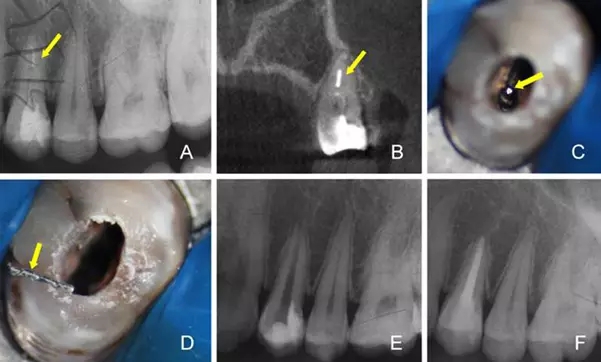

A:術(shù)前X線根尖片 B:術(shù)前CBCT定位折斷器械位置 C:顯微鏡下尋找折斷器械 D:顯微鏡下隱裂紋清晰可見 E:術(shù)后X線根尖片 F:一年后復(fù)查X線根尖片

4.根管內(nèi)折斷器械的取出

器械折斷于根管內(nèi)是根管治療主要并發(fā)癥之一,有效取出根管內(nèi)折斷器械可提高根管治療的臨床療效。傳統(tǒng)方法取出率低,并且容易發(fā)生側(cè)穿或?qū)⒄蹟嗥餍低葡蚋飧钐?。手術(shù)顯微鏡在折斷器械取出過程中能提供良好的視野,充分暴露折斷器械,是根管內(nèi)折斷器械順利取出的必要條件。顯微鏡輔助超聲技術(shù)能安全、有效取出大部分折斷器械,是目前最常用的折斷器械取出方法[7,8]。首先,術(shù)前要通過研讀X線片對折斷器械的類型、位置、長度和根管的彎曲度、厚度進行判斷,以初步評估取出根管內(nèi)折斷器械的可行性及預(yù)后。在手術(shù)顯微鏡下,建立直線通道至折斷器械冠方,使用超聲器械逐步去除折斷器械四周的牙本質(zhì),游離折斷器械的中上部,使折斷器械上段與根管壁間有一定的間隙。在此過程中要盡可能少磨除過多牙本質(zhì),防止降低牙體的抗折強度,造成根管壁的穿孔。當(dāng)逆時針圍繞折斷器械振動時,多數(shù)情況下折斷器械會逐漸松動,隨沖洗液漂出彈出[9]。